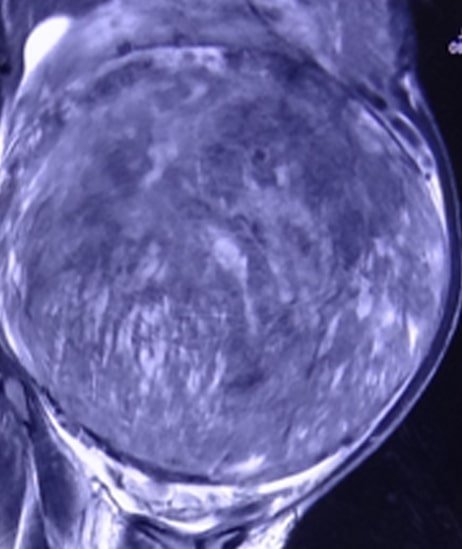

35 years lady presented with history of weight loss, gradually increasing abdominal swelling and decreased food intake. On examination she was found to have huge abdominal swelling. She was evaluated with MRI abdomen and image guided biopsy.

MRI showed a very large intraabdominal mass of approx. 30X25cm. This mass was occupying almost whole of the abdomen and displacing all the organs to side. Its was not possible to confirm organ of origin. Image guided biopsy was not conclusive.